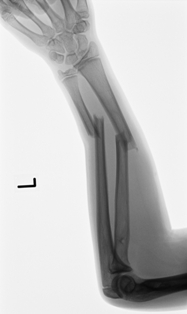

Kompletter Unterarmbruch bei einem 13 jährigen Schüler. Stabilisierung der Speiche und der Elle mit je einem Titanmarkdraht. Die Drähte wurden nach 4 Monaten entfernt.

Kompletter Unterarmbruch bei einem 13 jährigen Schüler. Stabilisierung der Speiche und der Elle mit je einem Titanmarkdraht. Die Drähte wurden nach 4 Monaten entfernt.